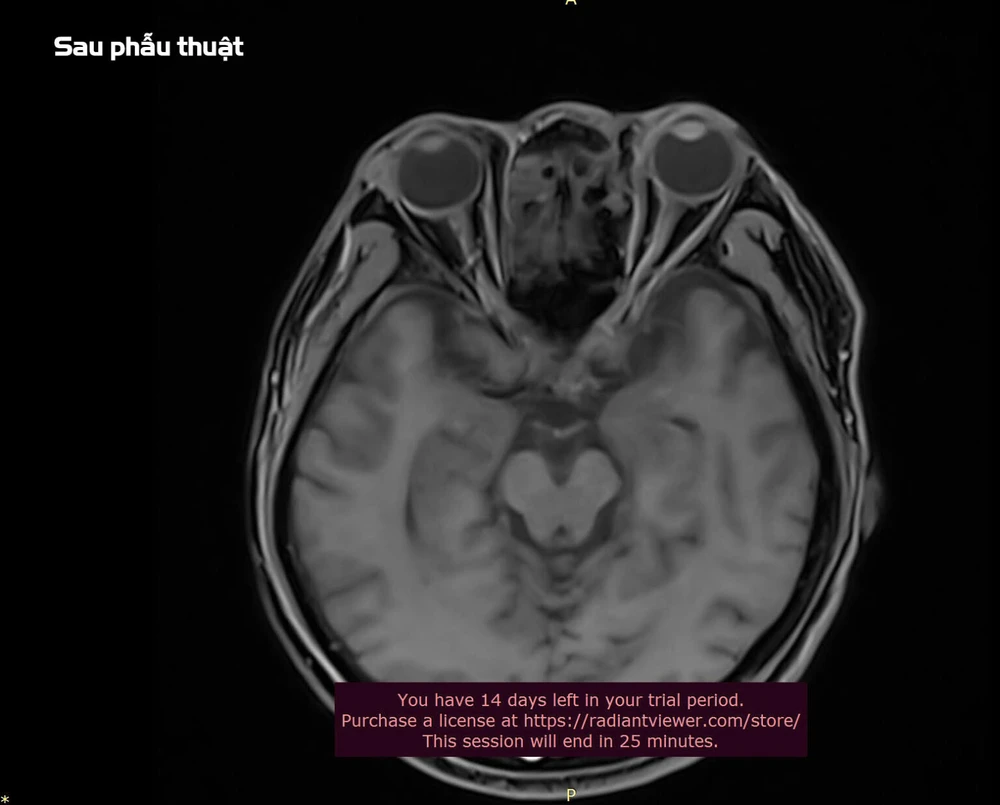

Kết quả chụp MRI cho thấy khối u nhầy kích thước 26x24x21mm xuất phát từ xoang sàng trước bên trái, đẩy lồi vào tổ chức phía sau hốc mắt và chèn ép cơ thẳng trong.

Phẫu thuật thành công ca u nhầy xoang sàng xâm lấn hốc mắt. Ảnh: BVCC